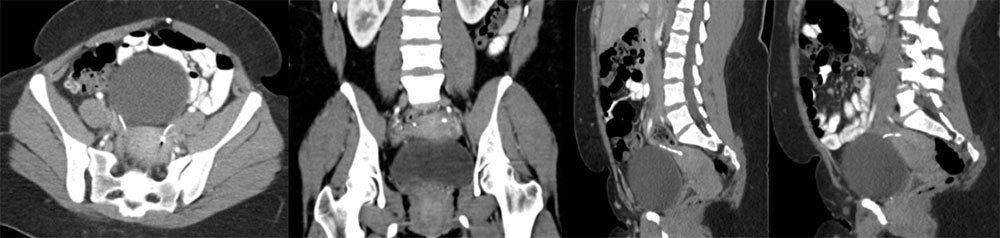

Case 11  55-year-old man with a pancreatic mass and history of recent inguinal hernia repair. Axial (A) and coronal MPR (B) CT images of the pelvis reveal:

Case 11  55-year-old man with a pancreatic mass and history of recent inguinal hernia repair. Axial (A) and coronal MPR (B) CT images of the pelvis reveal:

Retained Surgical Sponge

Retained Surgical Sponge  This is another example of how the sponge marker is better displayed with 3D volume rendering |